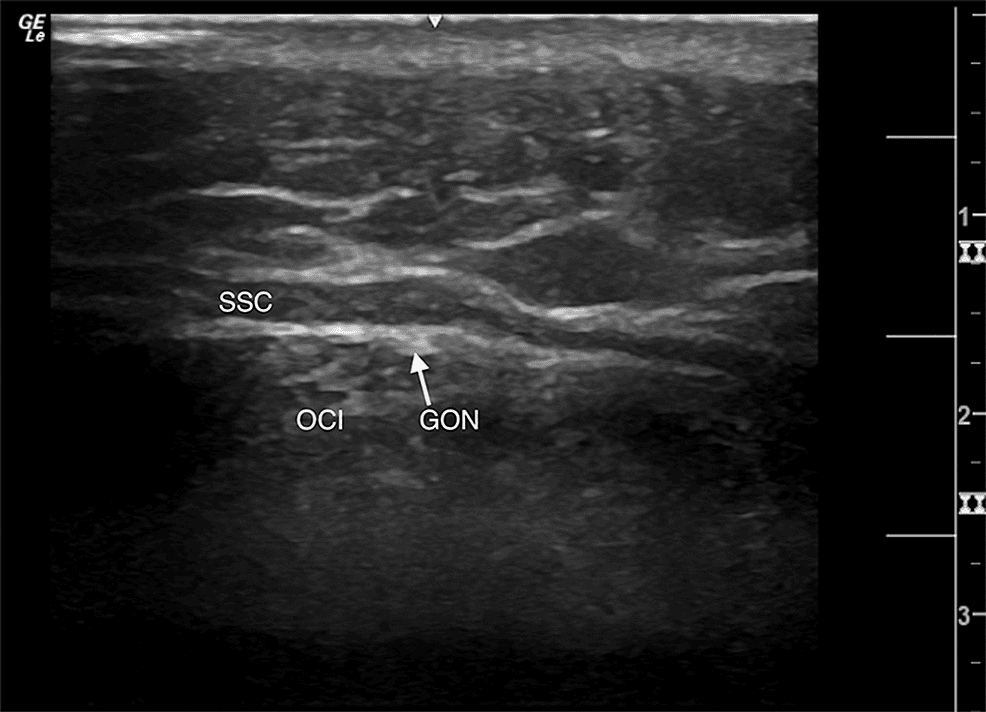

어깨통증 - 좌측 대후두신경(GON, Greater Occipital Nerve)을 고해상도 영상으로 관찰한 결과를 보여주는 영상입니다. 대후두신경은 후두부 Figure 1. 좌측 대후두신경(GON, Greater Occipital Nerve)을 고해상도 영상으로 관찰한 결과를 보여주는 영상입니다. 대후두신경은 후두부 두통과 목 통증의 주요 원인 중 하나로, 이 영상을 통해 신경의 정확한 위치와 주행 경로를 명확하게 확인할 수 있습니다. 이러한 해부학적 정보는 대후두신경 차단술이나 신경 치료 시 정확한 시술 부위를 결정하는 데 중요한 참고자료가 됩니다.

시술은 초음파를 이용하여 대후두신경의 정확한 위치를 확인한 후, 국소마취제와 스테로이드 혼합물을 신경주위 공간에 주사하는 방식으로 진행되었습니다. 기존의 맹목적 주사법과 달리 초음파 유도를 통해 신경의 정확한 해부학적 위치를 실시간으로 확인하면서 시술할 수 있어 효과와 안전성을 모두 높일 수 있었습니다.